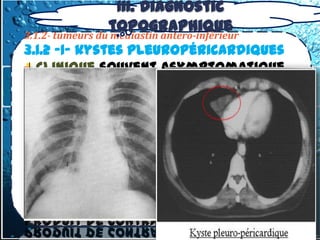

topographique

3.1.2- tumeurs du médiastin antero-

inférieur

3.1.2 -1- kystes

pleuropéricardiques

3.1.2- tumeurs du topographique

médiastin antero-inférieur

3.1.2 -1- kystes pleuropéricardiques

 Sont dérivés de récessus clos de la

cavité coelomique et sont bénins.

 Ils sont plus fréquents à droite

rarement à gauche ou post,

 = formations kystiques à parois

tendues, minces, sans adhérence au

poumon, contiennent un liquide (eau de

roche) dont la cytologie ne montre

aucun élément et la chimie est celle

d’un transsudat.

III. Diagnostic

3.1.2- tumeurs du médiastin antero-inférieur

Clinique souvent asymptomatique.

Rx thoracique:

Echo thoracique:

TDM.:

kyste , contenu liquidien sans

rehaussement apres injection du

produit de contraste.